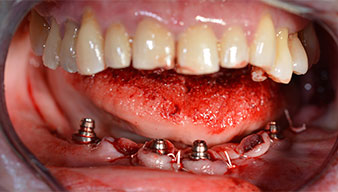

Dopo aver rimosso la dentatura residua dalla mandibola, la cresta alveolare viene esposta da 37 a 47.

Prima di tutto, è stato individuato il forame mentoniero come limite della struttura anatomica. Successivamente, l'osso corticale della cresta è stato lisciato con un manipolo e una fresa larga a rosetta (Fig. 4).

L'alta solidità è un requisito indispensabile per una ricostruzione immediata. Per garantirla, in questo caso il foro non è stato filettato. L'unità di perforazione Implantmed di W&H è dotata di una modalità speciale per questo scopo, che può essere selezionata direttamente ed è indispensabile in molte situazioni. In fase di posizionamento degli impianti, i giri finali hanno superato il valore di 32 Ncm e sono stati terminati a mano. In questi casi, consigliamo l'utilizzo della funzione autofilettante del sistema di implantologia e la rotazione degli impianti all'indietro e in avanti, per diverse volte. Questo permette all'impianto di assumere gradualmente la posizione finale, evitando un'eccessiva pressione all'osso (Fig. 14).

È stato avvitato un moncone angolato di 35 gradi per compensare la divergenza degli impianti distali. Ne risulta un profilo globale degli impianti situato il più perpendicolare possibile al piano occlusale. Questa situazione è un prerequisito per il posizionamento occlusale di protesi provvisorie e, successivamente, di quelle definitive (Fig. 15 e 16).

impianti

Fig. 15

Fig. 16